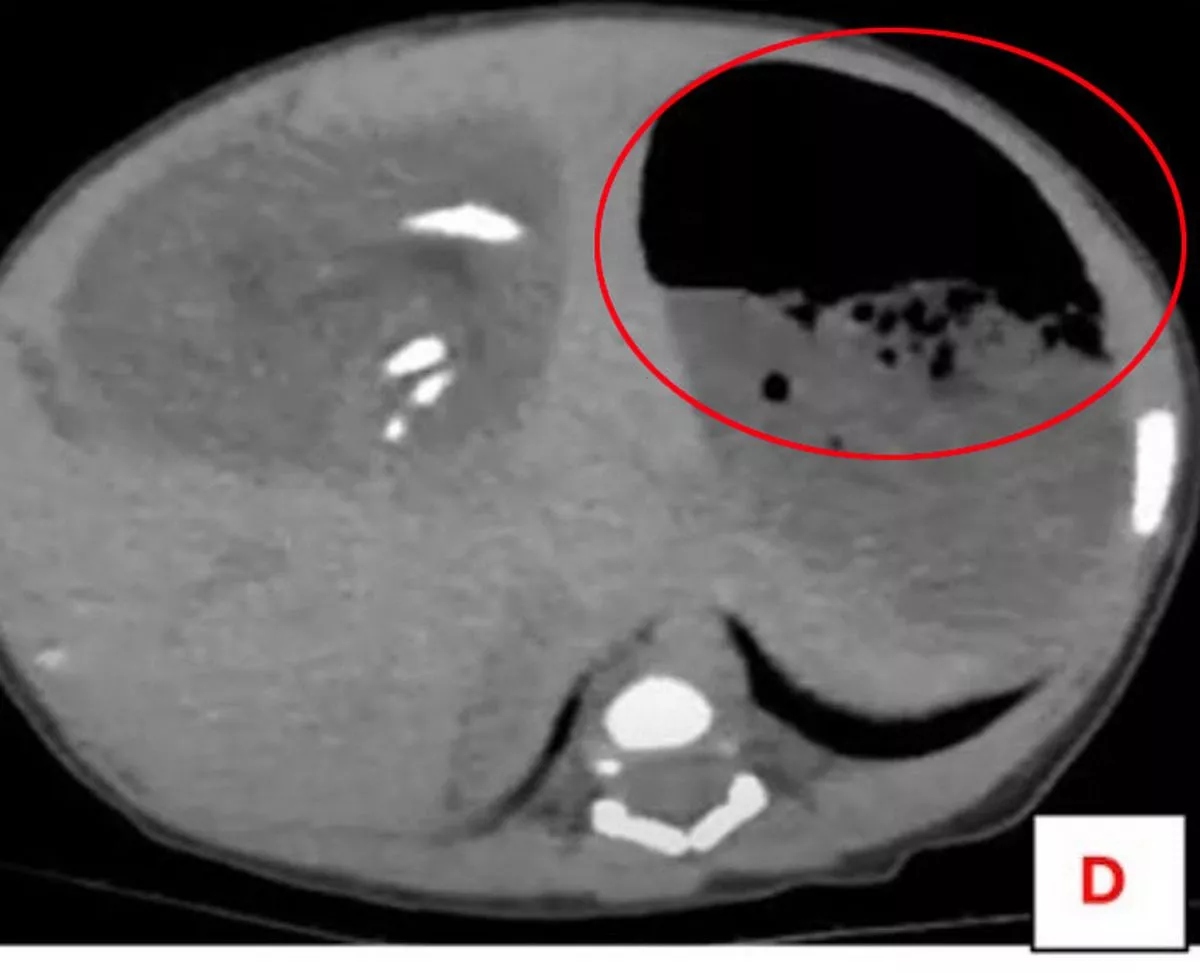

Chụp cắt lớp vi tính có cản quang ở dạ dày và xương chậu một lần nữa làm nổi bật khối u, lần này cho thấy các bộ phận xương bị biến dạng giống như xương dài, xương sườn, đốt sống, xương chậu và mô mềm.

Các bác sĩ có thể thấy thai nhi được nuôi dưỡng bởi một động mạch lớn và họ xác nhận phát hiện này là trường hợp thai trong thai – một dị tật cực kỳ hiếm gặp xảy ra khi một thai đôi ký sinh dị dạng phát triển bên trong cơ thể của anh chị em.